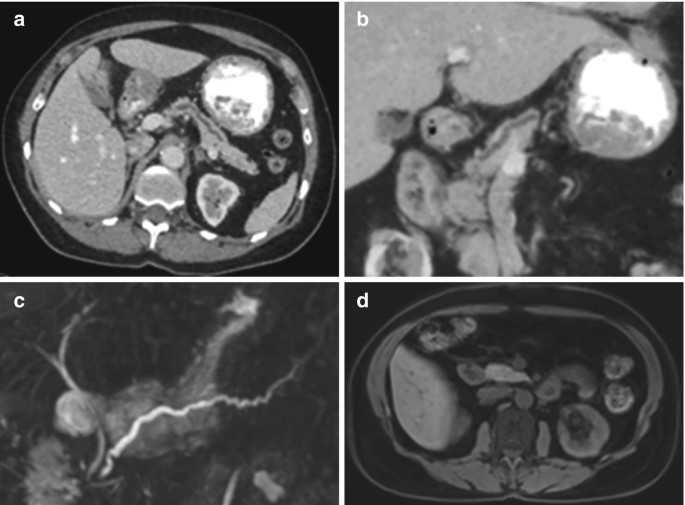

From link.springer.com

Ductal Dilatation without Perceptible Mass SpringerLink Differentials For Abdominal Pain Several other pivotal points can help narrow the differential diagnosis including (1) the time course of the pain, (2) peritoneal findings on exam, (3) unexplained hypotension, and (4) abdominal. Learn how to approach the differential diagnosis of abdominal pain in adults based on history, physical examination, and. Learn how to assess and manage patients with acute abdominal pain, a common. Differentials For Abdominal Pain.